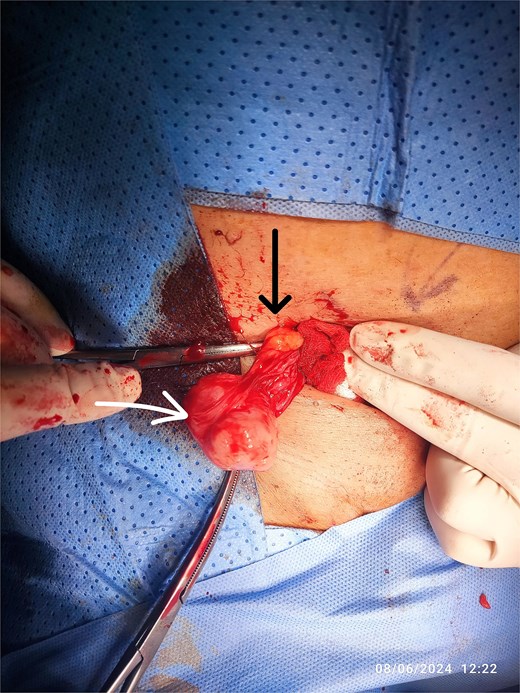

This procedure involved a wide local excision of the tumor bed down to the transversalis fascia, high ligation of the cord at the level of the deep ring, along with an orchidectomy, and excision of previous surgical scar (Fig. 3). The inguinal floor was reinforced with mesh to prevent future hernia formation.

Radical orchidectomy specimen, with marked inferior resection margin.

The patient recovered well from the second surgery, and his sutures were removed 2 weeks postoperatively. The second histopathology report confirmed complete resection with negative margins.